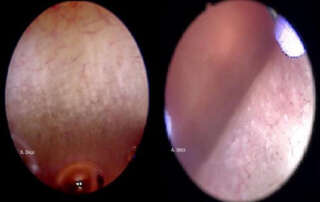

Diagnostic hysteroscopy: vagina and cervix. Micro-colpo-hysteroscopy